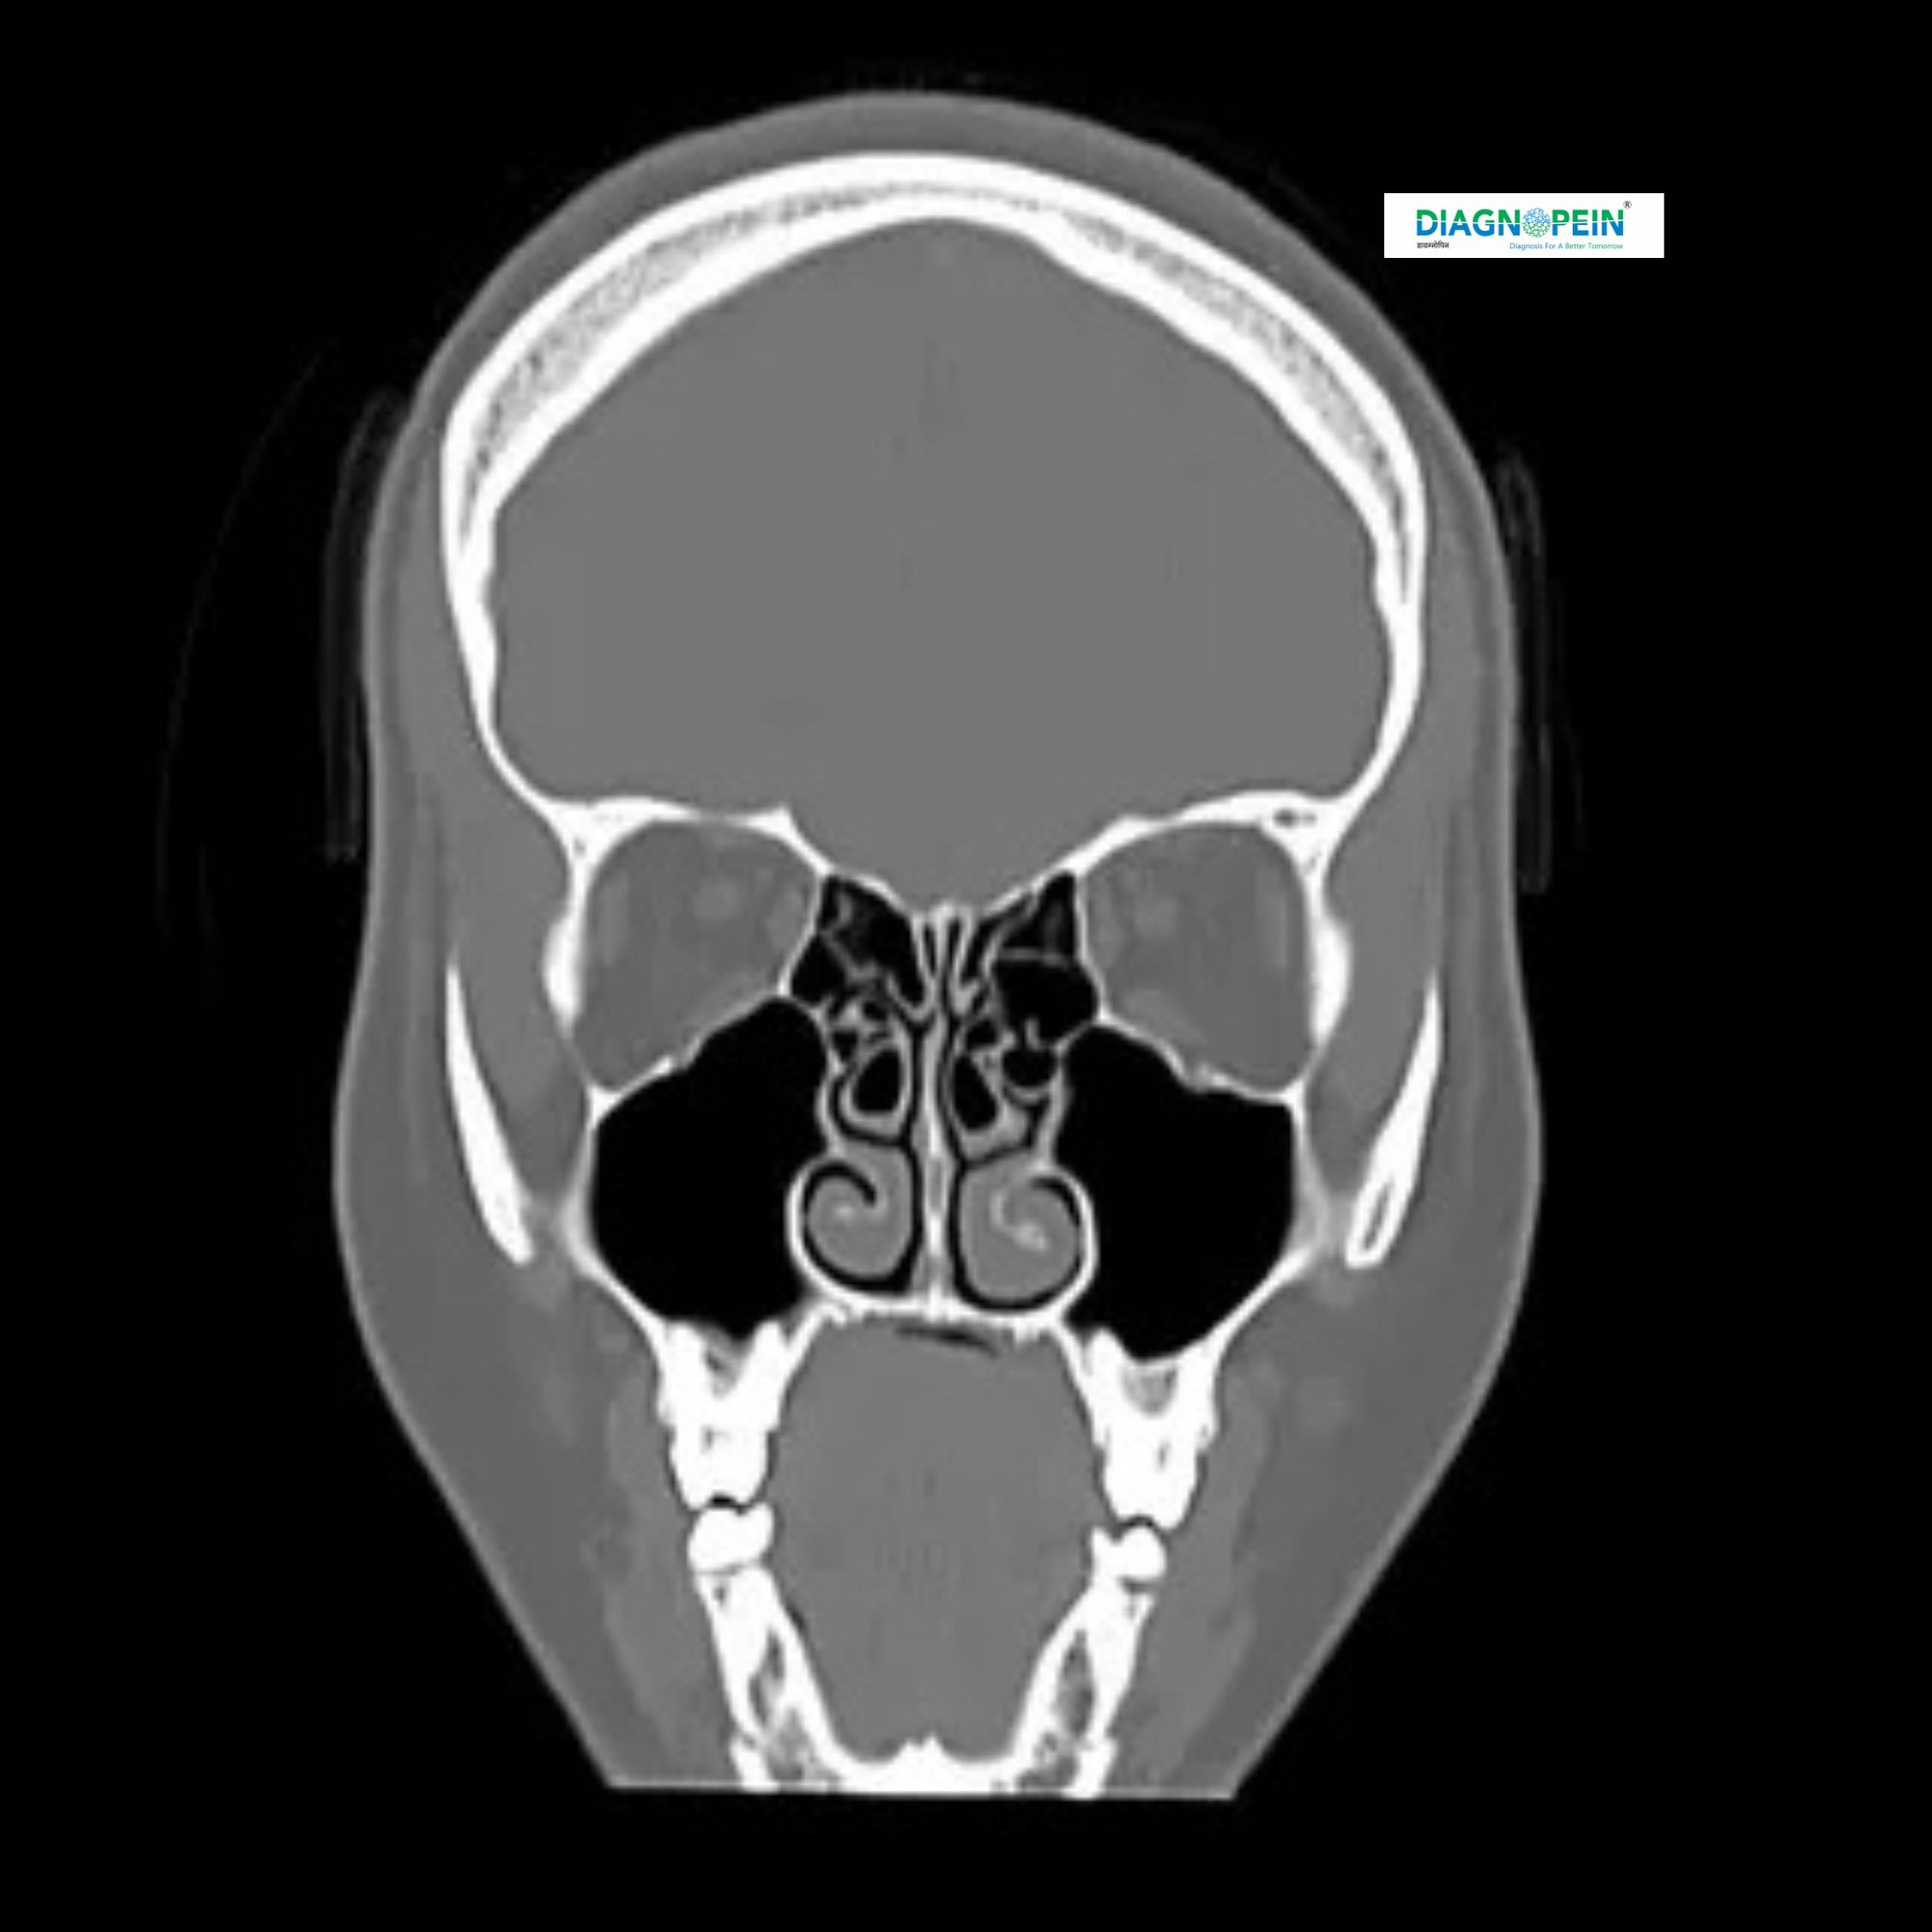

A CT Scan of the Para Nasal Sinuses (PNS) without contrast is a specialized imaging test that provides detailed 3D images of the air-filled spaces around your nose, eyes, and forehead. It is one of the most accurate diagnostic tools for identifying sinus infections, nasal blockages, bone abnormalities, polyps, or chronic sinusitis.

A CT PNS (Para Nasal Sinus) Scan Without Contrast uses X-rays and computer technology to capture cross-sectional images of your sinus cavities. Unlike a contrast-enhanced scan, it does not require any injection of contrast material, which means it’s faster, simpler, and more comfortable for most patients.

The scan provides a clear picture of:

1. Inflammation or infection in the sinuses

2. Deviation of the nasal septum

3. Bone fractures or structural issues

4. Sinus tumors or cysts

5. Airway obstruction or chronic sinus problems